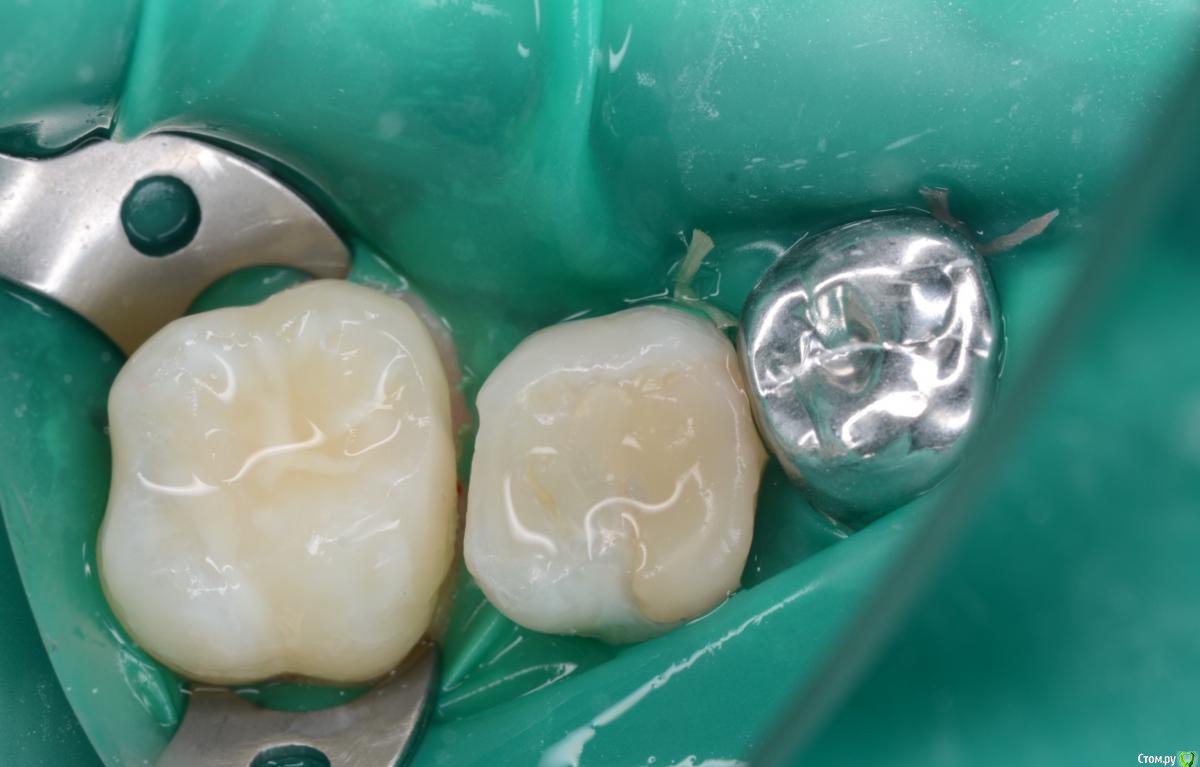

CRAZYDUCK Опубликовано 31 мая, 2018 Автор Поделиться Опубликовано 31 мая, 2018 Взрослых практически не лечу ( не очень мое это ). Вот ассистентка моя , Алинка . Сапожники без сапог , блин . Берегла зубы почти год для тренировки другой ассистентки , не дождалась . Вмешалась я. 6 Ссылка на комментарий